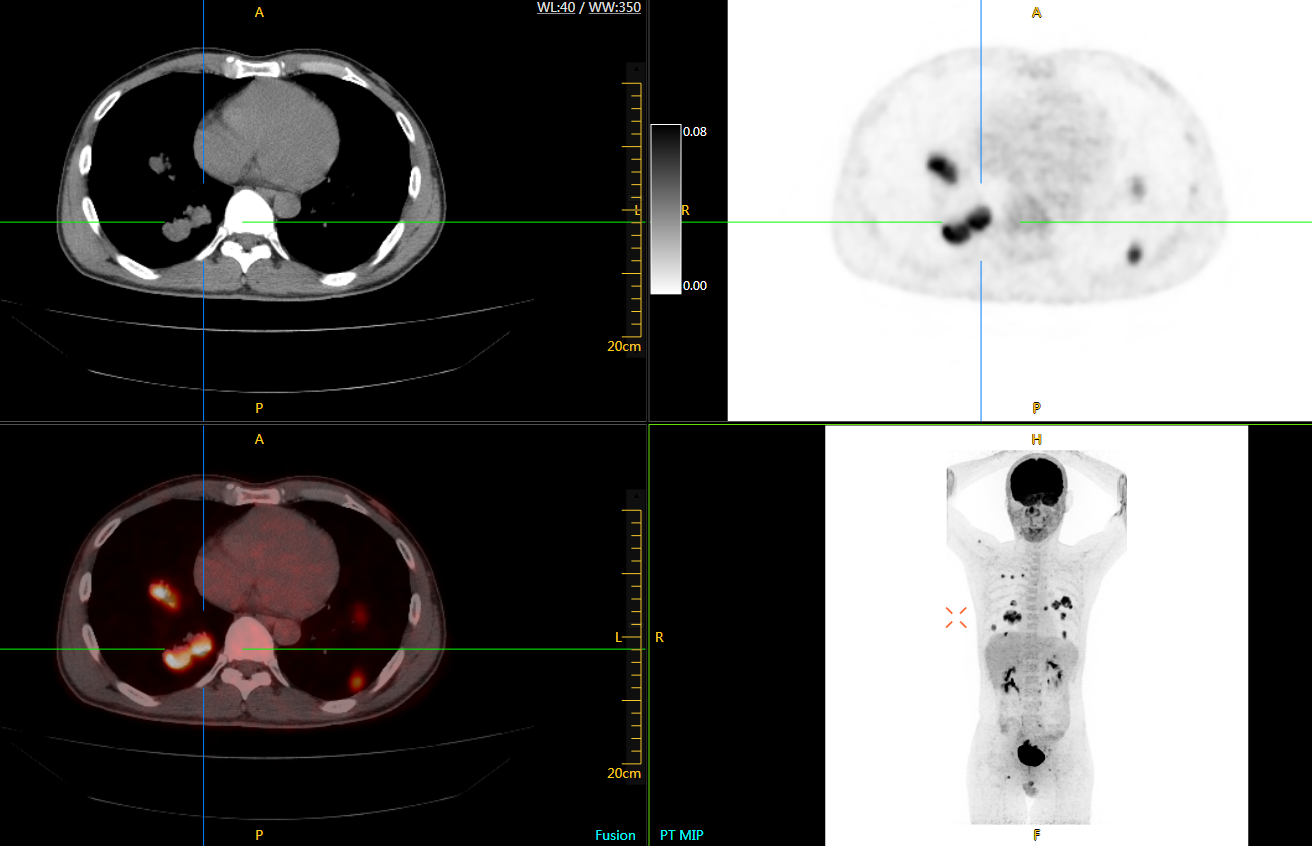

圖例

直腸癌

男,45歲,直腸癌術(shù)后9個(gè)月,發(fā)現(xiàn)肺占位

臨床診斷:直腸區(qū)術(shù)后改變,復(fù)發(fā)伴骶骨受累,雙肺多發(fā)轉(zhuǎn)移

肺癌轉(zhuǎn)移及復(fù)發(fā)

患者男性,66歲,七年前發(fā)現(xiàn)右肺肺癌,其間手術(shù)兩次,共切除兩個(gè)肺葉,復(fù)查;

診斷意見(jiàn),回腸轉(zhuǎn)移,右肺殘留部復(fù)發(fā)